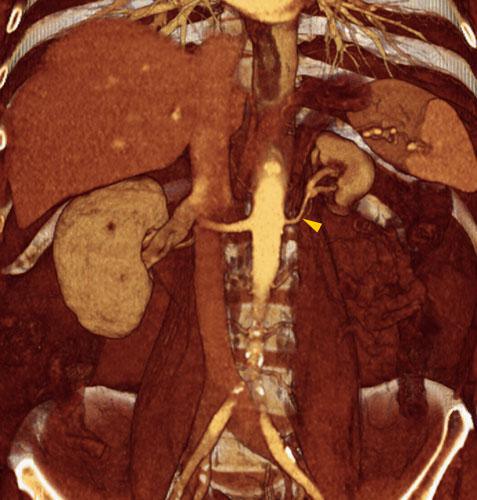

Hipoplasia renal 2

VR seccional. Visión coronal anterior. Se visualiza un riñón izquierdo con contornos lisos y de pequeño tamaño. Obsérvese la arterial renal izquierda (punta de flecha) sin estenosis y de un tamaño proporcionado al riñón